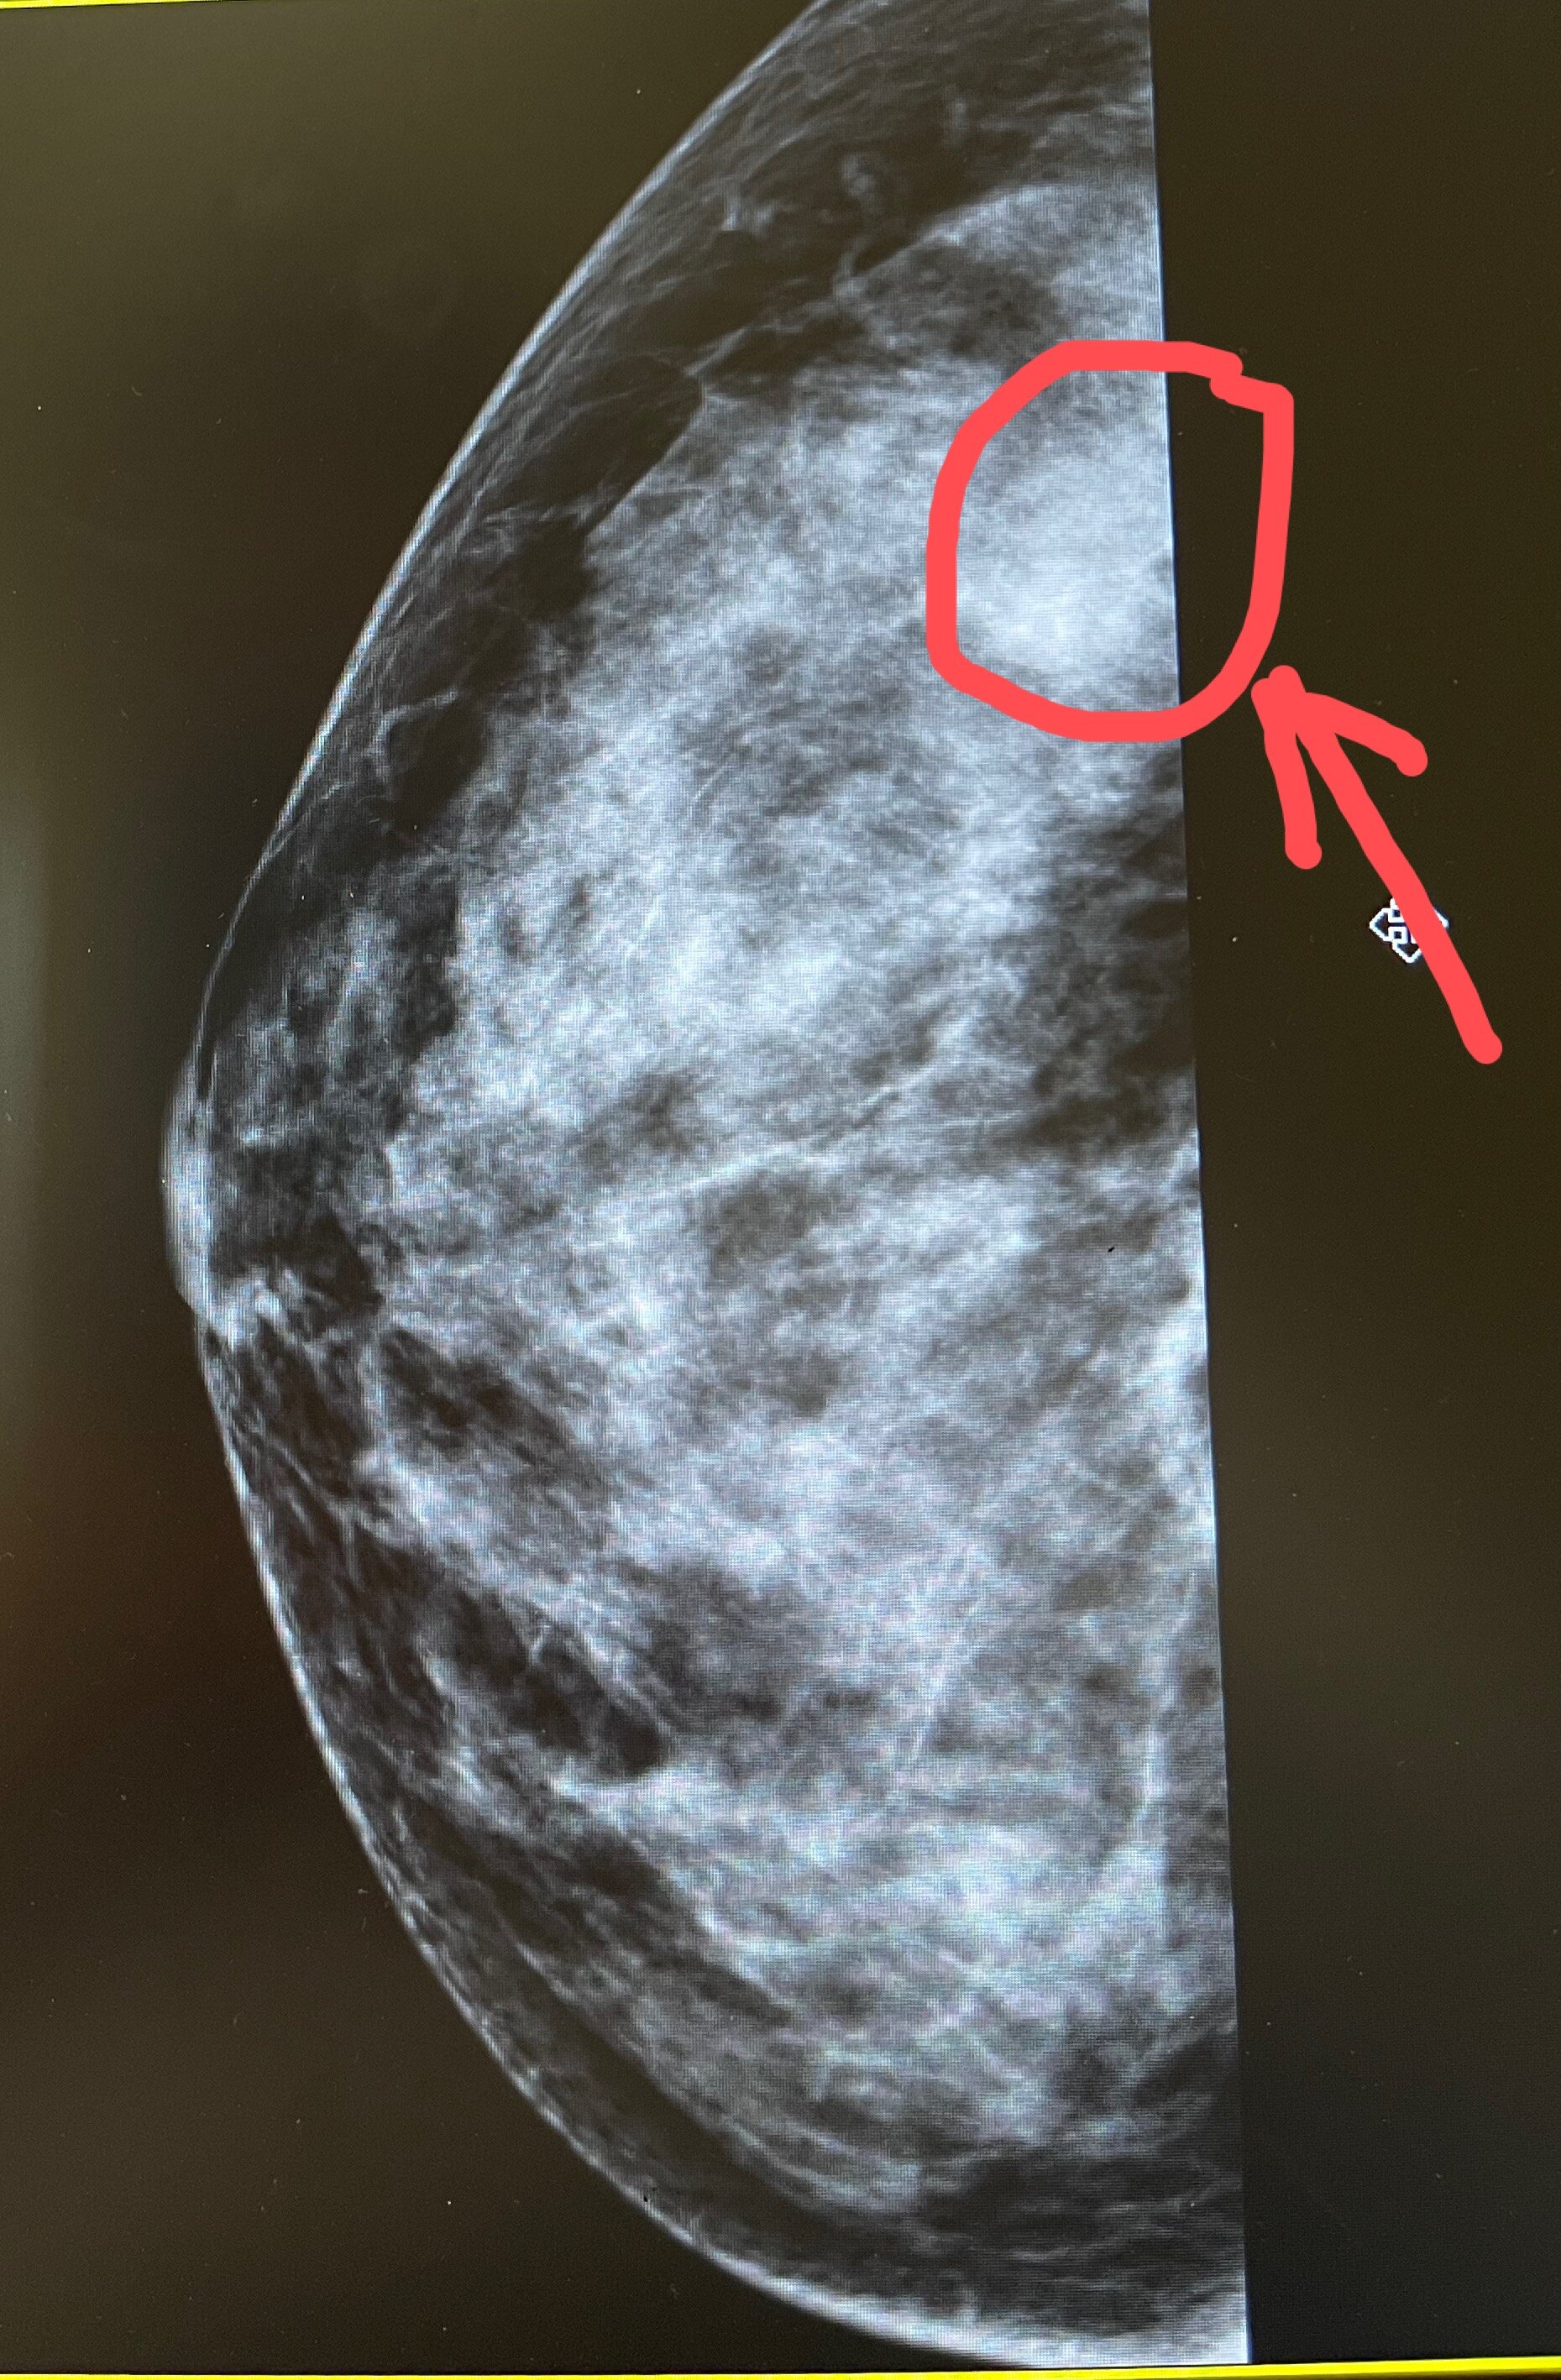

钼靶上的不对称致密影是怎么回事?

钼靶提示的不对称致密影80%都是钼靶拍片过程中正常组织重叠所形成的伪影。钼靶一般会拍头足位(CC位)和侧斜位(MLO位)两方位。仅在一个投照位置上见到,在其被确定具有三维占位特征之前,应描述为“不对称”。而真正的肿块在两个相互垂直(或近似垂直)的投照位置 上均能见到的有一定轮廓的占位性病变。为了排查一下乳房是否存在肿块,当钼靶提示乳腺存在不对称致密影时,首先需要结合乳腺彩超看看是否有乳房肿块的存在(彩超对乳腺肿块显示有优势,钼靶对乳腺钙化显示有优势),必要时再结合乳腺磁共振看看。王志威 副主任医师,医学博士中组部第十一批援疆专家,外科学博士毕业于上海交通大学医学院,擅长乳腺良恶性肿瘤的手术治疗及乳腺癌的化疗等规范化系统治疗,常规开展乳房结节、乳房肿块(如乳腺纤维瘤)的微创手术及乳房钙化、乳头溢液、乳腺炎、乳腺增生等乳腺常见疾病的诊疗。提倡基于最新国内外指南的规范化治疗,注重手术与美观的结合,重视在治疗疾病的同时给予患者人文关怀。曾荣获好大夫在线授予的“年度好大夫”,荣获医院年度“十佳医师”,“十佳好人好事”等荣誉。如果您觉得文章对您有帮助,欢迎点赞及写评论,您的认可是我科普的动力。